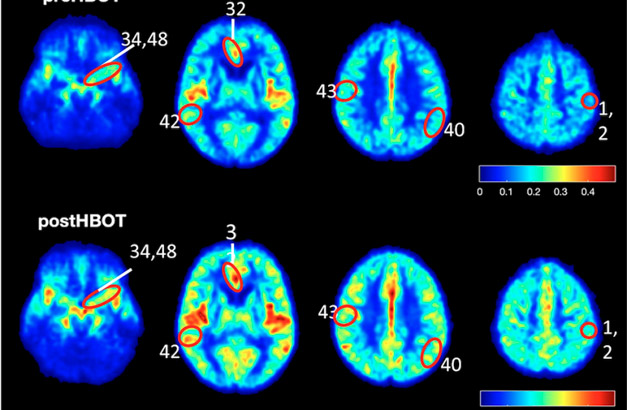

Los resultados del estudio muestran un flujo sanguíneo elevado y una mejor oxigenación en el cerebro de pacientes que sufren de deterioro cognitivo

Los efectos de la terapia en el cerebro se evaluaron mediante una resonancia magnética de perfusión de alta resolución.

Los resultados: 16% -23% de aumento en el flujo sanguíneo cerebral, 16,5% de mejora de la memoria y mejoras tanto en la atención como en la velocidad de procesamiento de la información.

«Después de una serie de tratamientos hiperbáricos, los pacientes ancianos que ya sufrían pérdida de memoria mostraron una mejora del flujo sanguíneo al cerebro, así como una mejora real en el rendimiento cognitivo», dijo el profesor Uri Ashery, también de la Universidad de Tel Aviv, que ayudó con el estudio. “En consecuencia, logramos demostrar el potencial latente de la medicina hiperbárica para el tratamiento de afecciones neurológicas que se originan en la hipoxia – es decir, una deficiencia de oxígeno que llega a las células”.